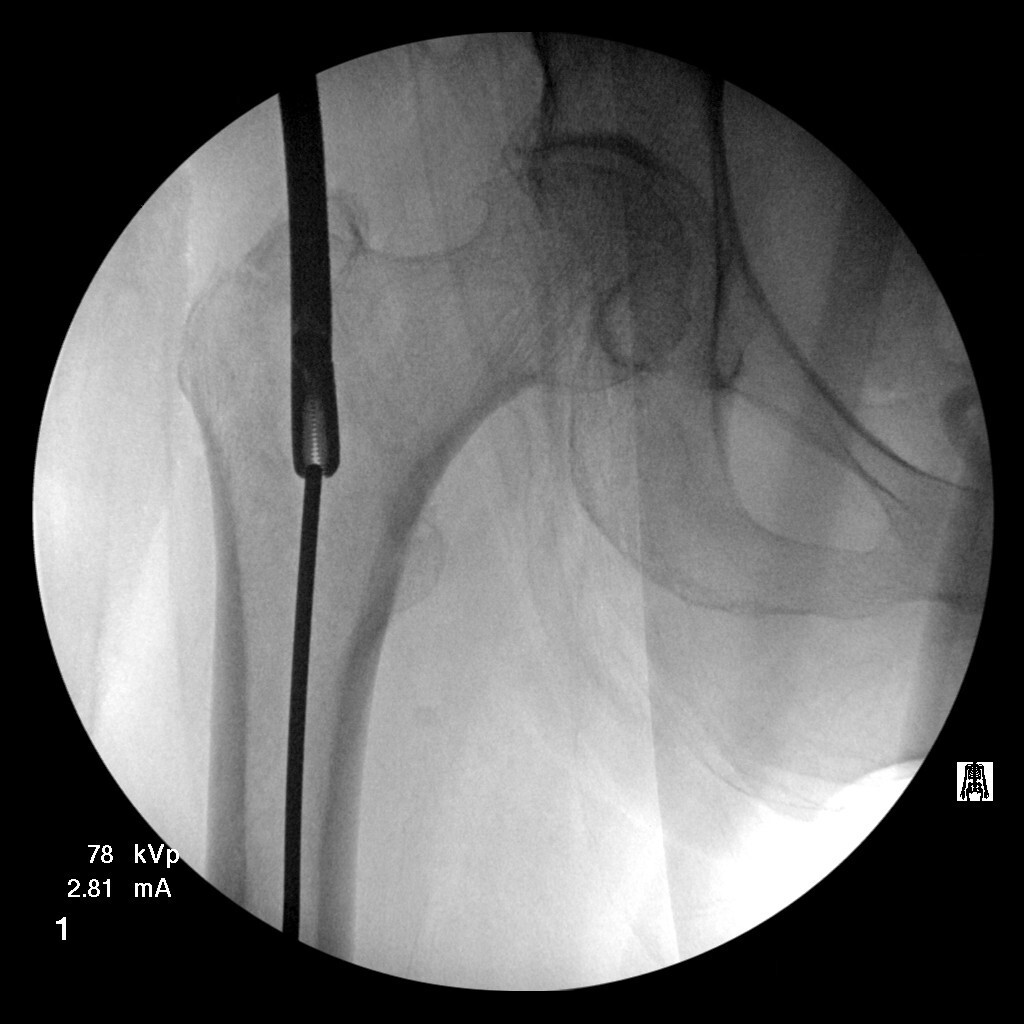

Multiple failed attempts were made to remove the guidewire using Kocher forceps, arthroscopic basket forceps, needle drivers, and Kerrison rongeurs (see Figure 1). Additional fluoroscopic images of the distal femur were subsequently obtained, revealing the guidewire to be inadvertently impacted into the subchondral bone of the distal femoral condyle (see Figure 2). Due to the inability to retrieve the guidewire using other extraction methods, a decision was made by the surgeons to remove the guidewire antegrade through the distal femoral condyle.